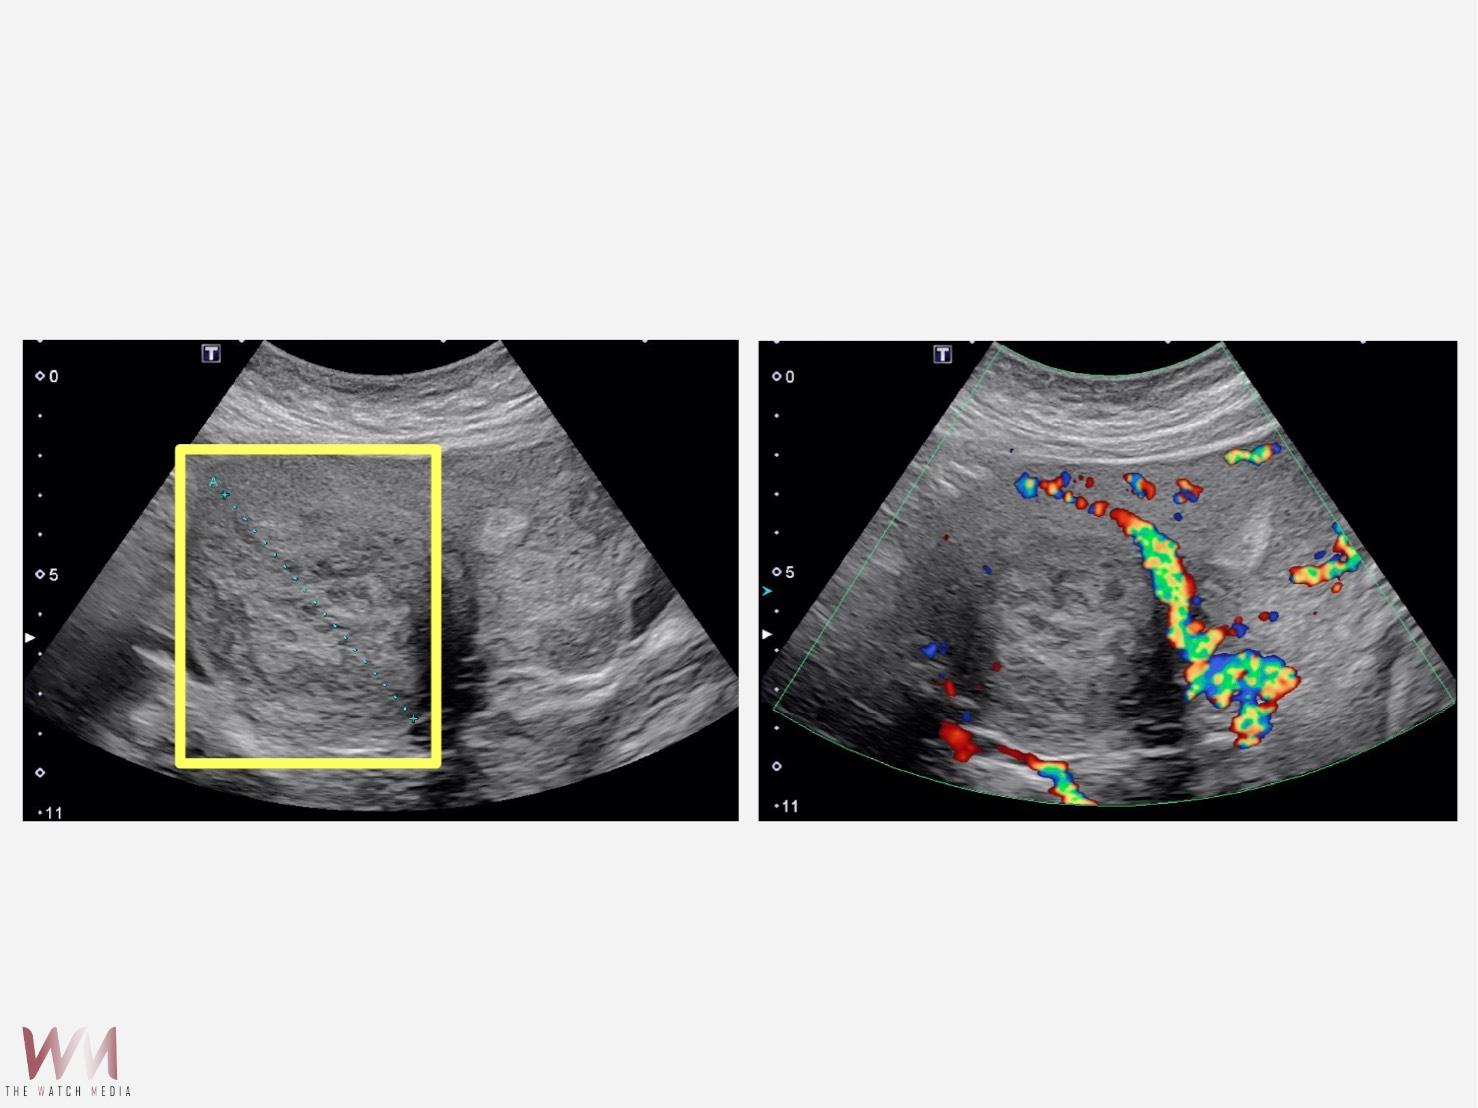

(觀傳媒中彰投新聞)【記者廖妙茜/台中報導】45歲的魏女士因為近半年來出現下腹部悶痛,所以到仁愛長庚合作聯盟醫院(大里仁愛醫院)婦產科林玉珊醫師門診求診,檢查後發現有下腹部悶痛合併壓迫症狀,竟然有7公分的肌瘤。經採用達文西機械手臂系統結合經陰道自然孔手術,於術後一週後即返家休養。由於手術並未在腹部留下傷口,讓魏女士感到非常驚訝,林玉珊醫師表示,傷口只是藏在看不到的地方,這不只是手術傷口變小,更代表病人能更快回到自己的生活與角色中。